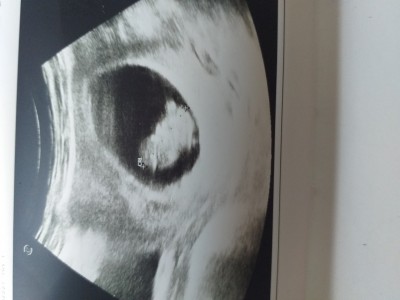

Mrb kızlar ben 9 haftalık hamileyim herkes öyle paylaşınca bende çok heves ettim hadi tahmin istiyorum bazıları sanki gerçekten biliyor keseye göre falan tahmin ediyorlar

Kese o kacaman siyah şey mi oluyor

Ewet canım yuvarlak olan varya bebeğinin dışında koruyan

Keseye göre kesin kız ama bebek hafif sola doğru bi şüpheye düştüm erkekte olabilir başka ultrason resmi varsa at bakalım bi daha